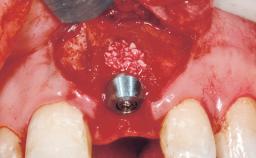

| Bone Augmentation | Horizontal|Staged |

| Augmentation Materials | Autogenous chips|Membrane |